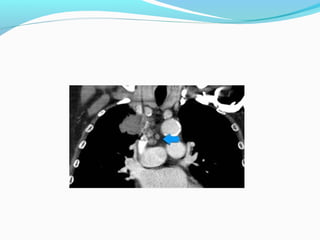

STAGE ??